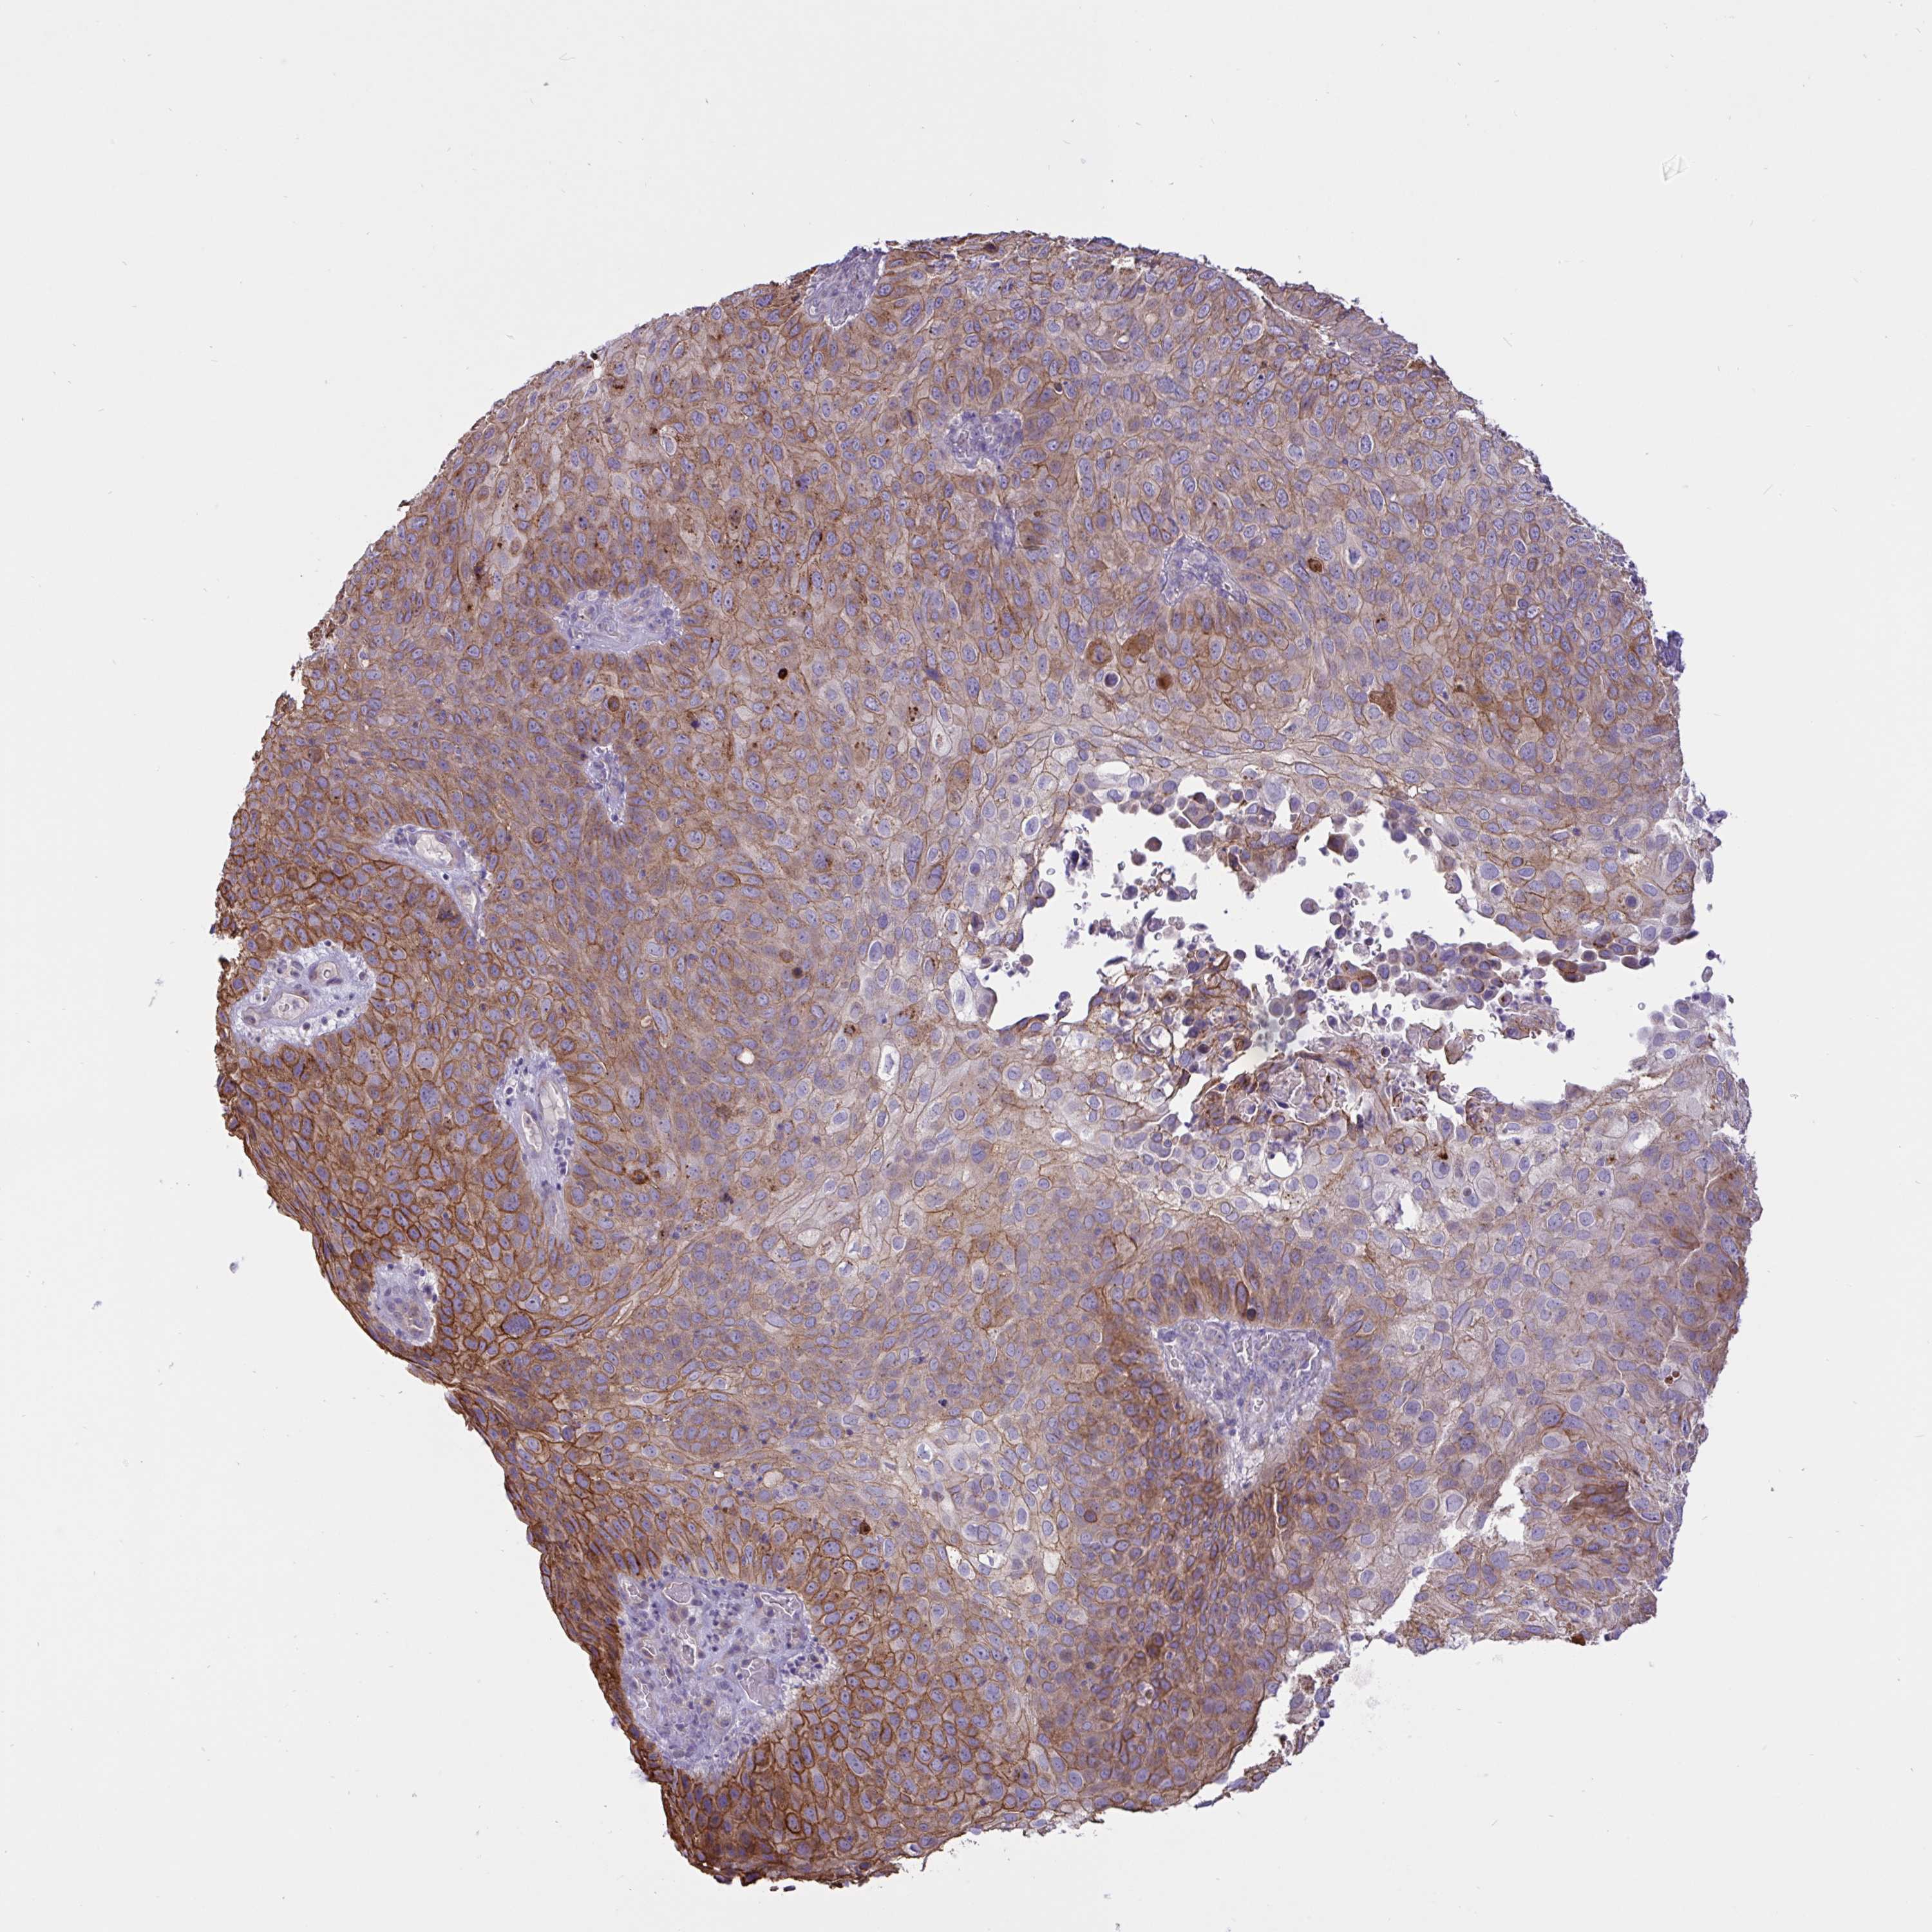

Basal cell and squamous cell cancer

SKIN CANCER - Protein expressioni

A mouse-over function shows sample information and annotation data. Click on an image to view it in a full screen mode. Samples can be filtered based on level of antibody staining by selecting one or several of the following categories: high, medium, low and not detected. The assay and annotation is described here.

Antibody stainingi

Antibody staining in the annotated cell types in the current human tissue is reported as not detected, low, medium, or high, based on conventional immunohistochemistry profiling in selected tissues. This score is based on the combination of the staining intensity and fraction of stained cells.

Each image is clickable and will lead to virtual microscopy that enables deeper exploration of all samples and also displays staining intensity scores, fraction scores and subcellular localization as well as patient and tissue information for each sample.

Antibody HPA049265

Antibody CAB037328

Staining

High

Medium

Low

Not detected

Intensity

Strong

Moderate

Weak

Negative

Quantity

>75%

75%-25%

<25%

None

Location

Nuclear

Cytoplasmic/membranous

Cytoplasmic/membranous,nuclear

Squamous cell carcinoma, NOS

Squamous cell carcinoma, metastatic, NOS